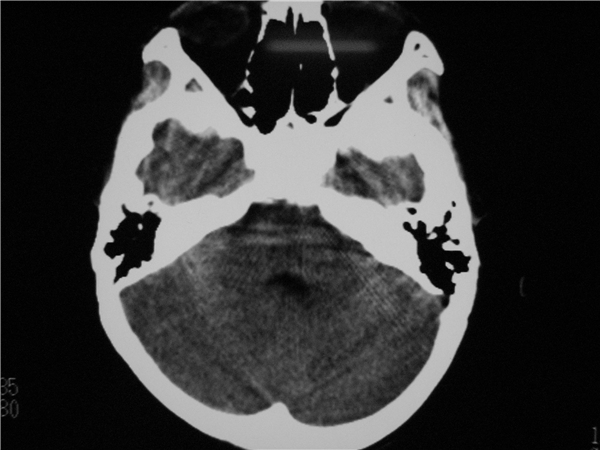

以下是引用随光逐影在2009-8-1 14:17:00的发言:[br]透明隔囊肿与vergae腔并存。

以下是引用zjzjr在2009-8-1 14:51:00的发言:[br]五、六脑室形成。